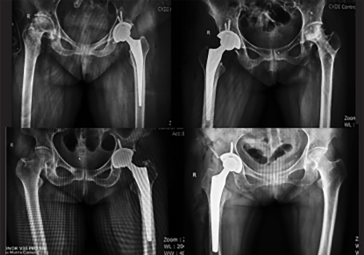

· 精準(zhǔn)執(zhí)行手術(shù)方案,消除徒手操作誤差。

· 髖關(guān)節(jié)置換:髖臼+股骨雙側(cè)規(guī)劃